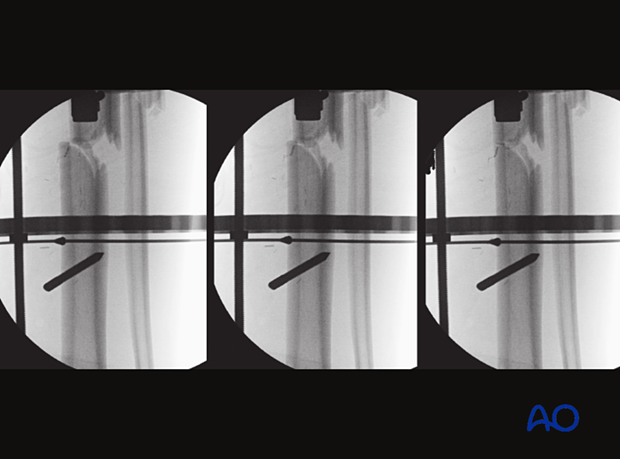

The AP and lateral views show that the proximal and distal positioning wires have achieved good alignment of the frame and bone and appropriate soft-tissue clearance.